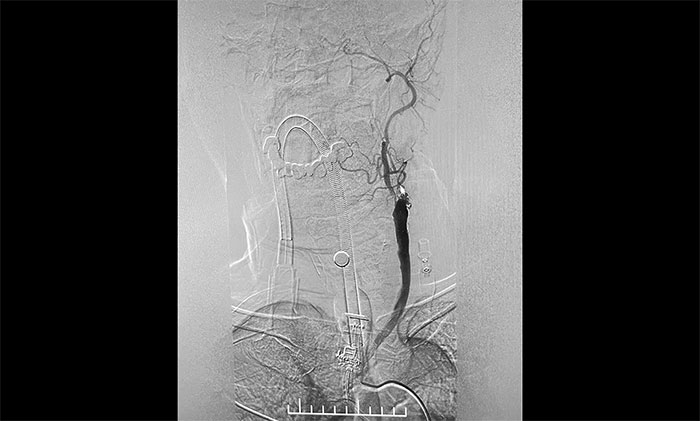

脑血管造影显示,左颈总动脉起始段、下段中度狭窄,左颈外动脉起始段重度狭窄,左颈内动脉起始段闭塞,远端颈内动脉缓慢显影至眼动脉;左椎动脉、左大脑后动脉、基底动脉显影,左椎V4段经侧枝向左侧枕动脉代偿供血至左颈外动脉;右颈内动脉起始段轻度狭窄。

▲ DSA确诊左侧颈内动脉闭塞